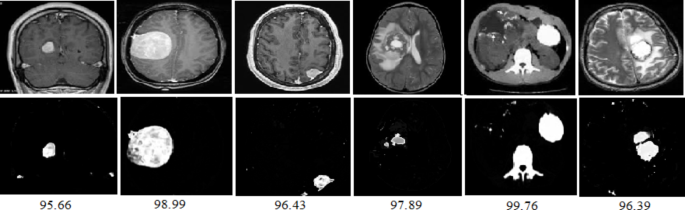

In this section, the results are shown for the segmented tumor from tumor images using the proposed GKEIFCM algorithm are shown in Fig. 8 and their accuracies are calculated.

Segmentation of tumors with accuracies in MRI brain images for the proposed GKEIFCM method.

Table 7 shows the results of accuracy for the segmented tumors. It can be seen that FCM_S1 method produces 92.83% and 92.54% accuracies noted as least value for 3%, 7% of noises respectively, and FLICM method results least for 5% of noise with 91.77 when compared to the proposed GKEIFCM algorithm.